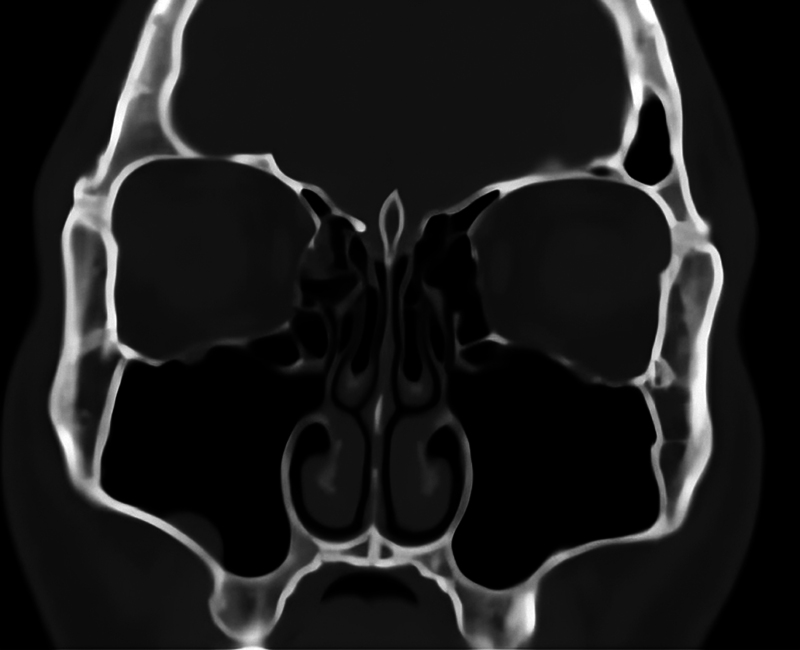

钩突(uncinate process, UP)是口鼻道复合体和中道中最重要和不变的标志。目的利用计算机断层扫描(CT)识别未发表的UP变异,并对其进行分类。方法对110例(220侧)旁鼻部CT进行扫描。轴向图像通过多平面重新格式化获得,以捕捉其他平面的精细细节。结果120例(220侧)CT扫描中,1型UP占84.5%,2型UP占12.3%,3型UP占3.2%,性别差异无统计学意义;中位UP占81.9%,垂直UP占16.3%,侧位UP占0.9%,缺失UP占0.9%,性别差异无统计学意义。总计8.63%的UPs采用了气动方式。结论本研究提高了外科医生和放射科医生对UP的认识,同时创建了一个标准的分类和描述,作为耳鼻喉科医生和放射科医生之间的共同语言,也可用于培训。

Introduction  The uncinate process (UP) is the most important and constant landmark in the ostiomeatal complex and the middle meatus. Objective  To identify the UP variations that have not been published before and establish a categorization using computed tomography (CT). Methods  The current study was carried out on 110 paranasal CT scans (220 sides). Axial images were acquired with multiplanar reformats to capture delicate details in other planes. Results  Out of 120 CT scans (220 sides), the UP was found to be of type 1 in 84.5%, type 2 in 12.3%, and type 3 in 3.2%, without significant diferences between genders, and it was found to be medialized in 81.9%, vertical in 16.3%, lateralized in 0.9%, and absent in 0.9%, without significant differences between genders. A total of 8.63% of the UPs were pneumatized. Conclusion  The present study improves surgeons' and radiologists' knowledge of the UP, while creating a standard classification and description to be used as a common language between otorhinolaryngologists and radiologists, which could also be used for training.